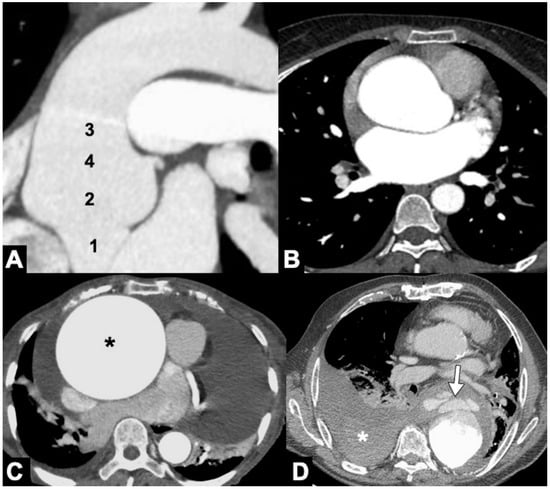

- A low-dose, non-gated, non-contrast phase, with coverage from the lung apex to the lower abdomen, which is useful to evaluate the presence of aortic intramural hematoma, displaced intimal calcification, surgical material, and high-density pericardial, pleural, or mediastinal blood (Figure 2). The radiation dose of the non-contrast phase should be kept low by using wider collimation and low tube potential with concomitant reduction in the tube current. Nowadays, dual-source technology provides a virtual non-contrast phase obviating the need to acquire a non-enhanced phase.

- A non-gated delayed phase (about 70 s delay) obtained to assess for late filling of a false lumen (FL), to clearly depict abdominal organ malperfusion, contrast extravasation due to aortic rupture and to evaluate peri-adventitial enhancement indicating acute aortitis.